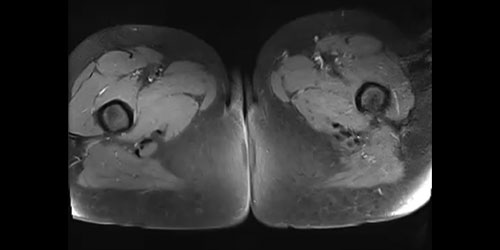

46 yaşındaki erkek hasta, 5 aydır süren bel ağrısı ve oturma güçlüğü şikayetleriyle başvurdu. Sakroiliak bölgedeki kitleye yapılan biyopsi sonucu kondrosarkom tanısı kondu. Metastaz saptanmadı. Tümör temiz sınırlarla çıkarıldı, bölge rod ve vidalarla stabilize edilerek hasta takibe alındı.